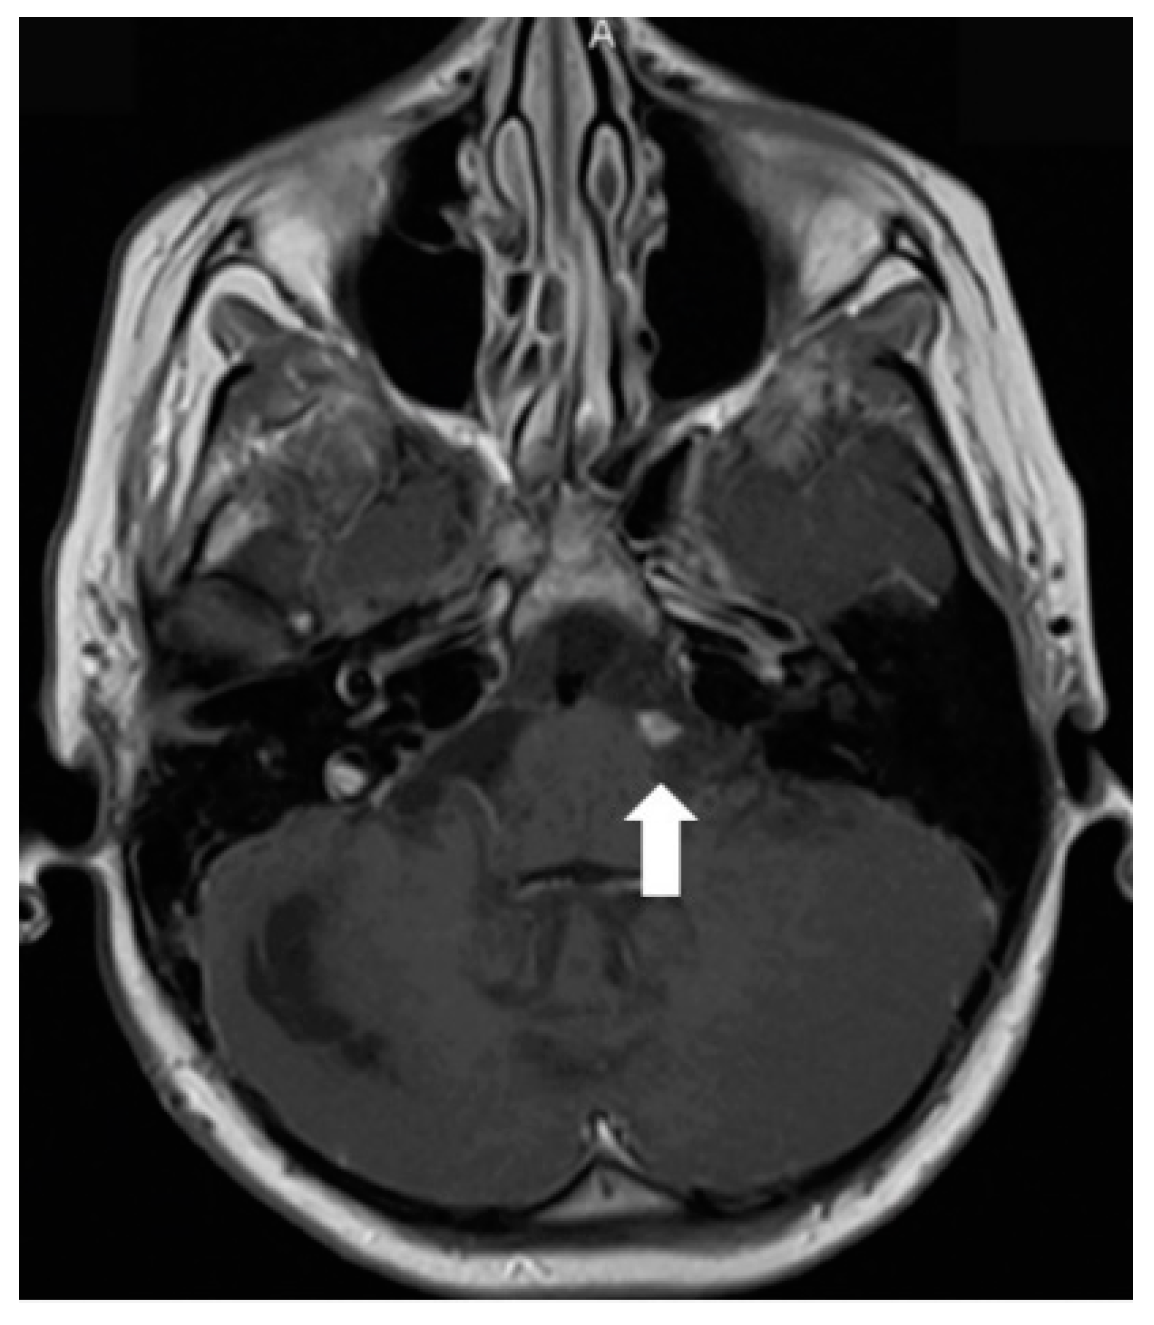

In July 2011, a 16-year-old girl was admitted to Hospital of Lithuanian University of Health Sciences Kauno klinikos due to severe headache, vomiting, and vertigo lasting 2 days. She had a half-year history of similar paroxysms usually beginning with numbness in hands or in one side of face or leg. Neurological examination revealed right-sided peripheral facial paresis, horizontal nystagmus, painful exit points of branches of the right trigeminal nerve, slight deviation of the uvula to the right, right-sided hemiparesis, and cerebellar ataxia. Moreover, papilledema was observed. Brainstem evoked potentials response audiometry showed no clear waves on the right side although hearing was normal. Magnetic resonance imaging (MRI) of the head demonstrated a hyperintense mass on T2W/FLAIR images with heterogenous enhancement in the right cerebellopontine angle cistern and internal auditory canal (Figure 1). All figures in this manuscript are non-published and original.

Figure 1.

Initial MRI of the brain at our clinic (July 2011): (A) Axial T2W/FLAIR and (B) coronal T2W images demonstrate a hyperintense mass in the right cerebellopontine angle cistern and internal auditory canal. (C) Axial and (D) coronal T1W postcontrast images show heterogenous enhancement in the referred area.